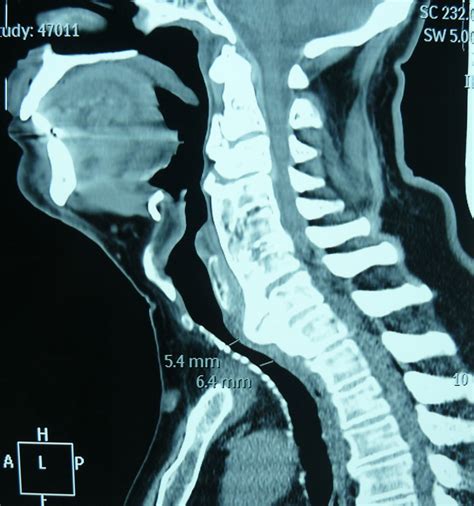

If you suspect that your symptoms are related to bone spurs, a healthcare professional will perform a physical examination to test your reflexes, muscle strength, and range of motion. To confirm the diagnosis of osteophytes in cervical vertebrae, imaging is typically required.

• X-rays: Highly effective at visualizing the bony projections and narrowing of the disc space.

• MRI (Magnetic Resonance Imaging): Provides detailed images of soft tissues, nerves, and the spinal cord, allowing doctors to see if the bone spurs are compressing neural structures.

• CT Scans: Used when more detailed bony imaging is required than what an X-ray can provide.